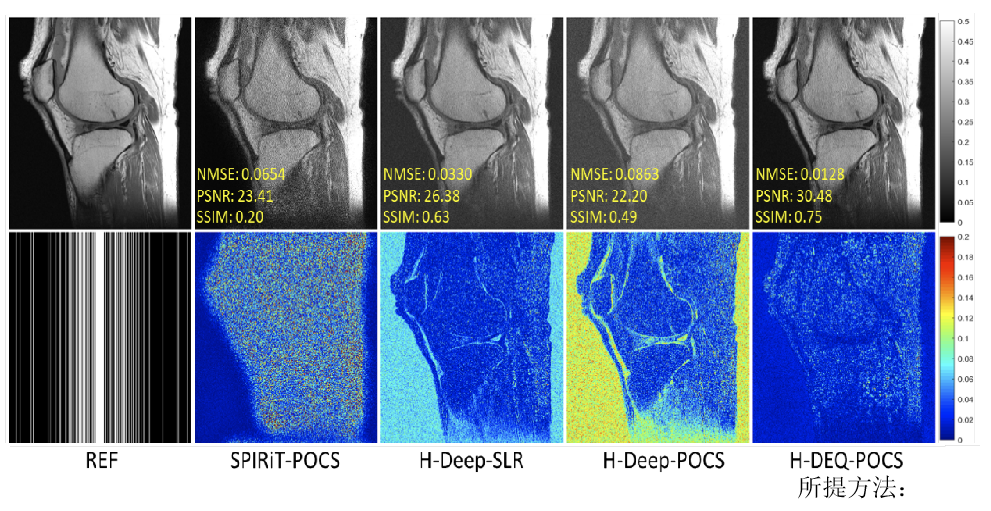

其次,针对目前主流深度学习快速重建方法可靠性不足的问题,提出了零阶算法展开网络的思想,利用网络表示正则化子零阶信息(正则化子本身),增强了网络学习的可解释性,保证了网络算法收敛性和鲁棒(正则)性。实验证明(图2),该方法重建图像质量明显优于传统方法。研究成果发表在医学成像领域著名期刊IEEETransactions on Medical Imaging。

图2.测量噪声扰动下,4倍加速重建结果